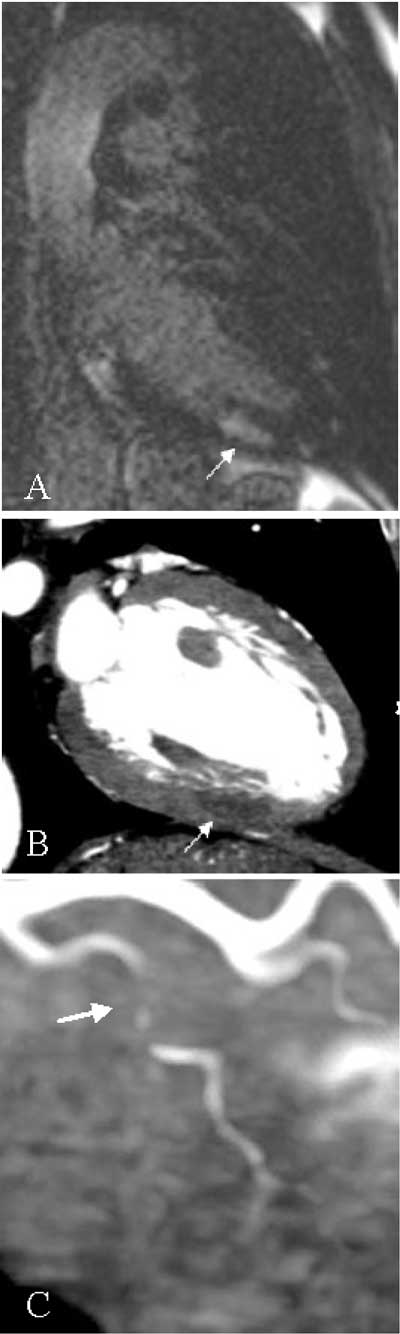

A 53-year-old male was admitted for typical acute chest pain. The ECG showed a mirror image of posterior myocardial ischemia. Initial biology was normal but cardiac markers (creatine kinase and troponin) rose later. Echocardiography did not reveal any hypokinetic myocardial segment. There was no left ventricular dysfunction or valvular disease. There was no pericardial effusion or aortic dissection image. This patient was treated as a “non-ST segment elevation myocardial infarction” (NSTEMI), also called subendocardial myocardial infarction. A selective coronary angiography (SCA) was performed the next day and after careful examination by several experts, no coronary lesion was detected. Left ventriculography was also normal. Cardiac MRI was then performed and revealed a late focal subendocardial enhancement, located in the mid infero-posterior myocardial segment (Fig. A, arrow). This lesion appeared to be ischemic, despite normal SCA. Computed tomography coronary angiography (CTCA) was finally done, showing a hypodense image, with also an ischemic aspect, in the same subendocardial area (Fig. B, arrow) as observed on MRI. Furthermore, CTCA detected tight luminal narrowing with hypodense material (soft atheroma or clot) in a circumflex branch (Fig. C, arrow), corresponding to the suspected ischemic territory. In this case, CTCA both confirmed ischemic etiology and identified culprit artery missed by SCA.

Figures A–C